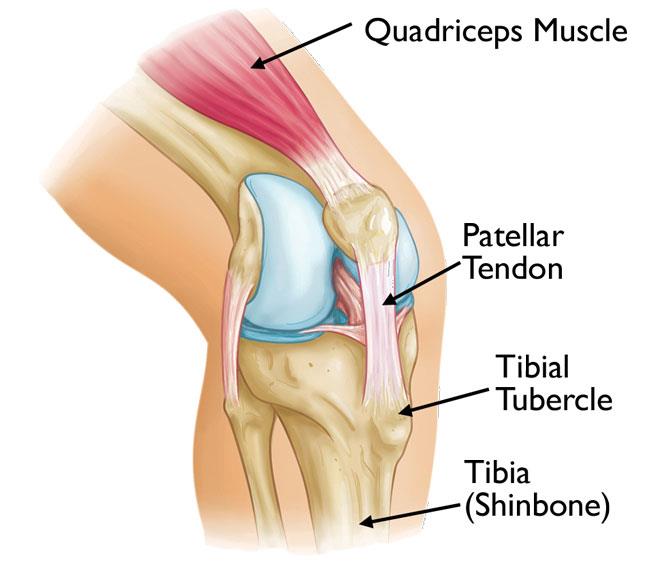

Where or Where Has My Patella Gone Direct Orthopedic Care 2024, Patella Kneecap Anatomy and Function 2024, Patellofemoral Pain Syndrome OrthoInfo AAOS 2024, The Patella Surface Anatomy Functions Dislocation 2024, Patella Wikipedia 2024, Patellar Fractures Broken Kneecap OrthoInfo AAOS 2024, Patellofemoral Joint Structure Function Conditions 2024, Patellofemoral Joint Physiopedia 2024, Patellar region Flashcards Quizlet 2024, Patella Injury Treatments Knee Surgeons Consultants Yorkshire 2024, Patella Anatomy function and clinical aspects Kenhub 2024, Patellar Tendonitis Jumper s Knee Johns Hopkins Medicine 2024, ITB vs Patellofemoral Pain Syndrome Symptoms Knee Pain In Runners 2024, Patellofemoral Pain Syndrome OrthoInfo AAOS 2024, Patella Anatomy function and clinical aspects Kenhub 2024, Patellar Tendonitis Jumpers Knee Symptoms Diagnosis Treatment 2024, Patellofemoral Pain Syndrome Rural Physio at Your Doorstep 2024, Patellar tendinitis Symptoms causes Mayo Clinic 2024, Patella Femoral Syndrome Montgomery Massage Therapy 2024, Jumper s Knee Symptoms in Kids Jumper s Knee Treatment 2024, Anatomy of Patella Bone and Spine 2024, Patellar Tendonitis Jumper s Knee Symptoms Causes Mount 2024, Anatomy Gruppo Bioimpianti 2024, Patellofemoral Pain Syndrome 2024, Patella Tendinopathy also known as Jumper s Knee Complete Physio 2024, Patellofemoral Pain Syndrome PFPS Symptoms Treatment 2024, Patellar Tendonitis 2024, Patellofemoral Joint Physiopedia 2024, How to avoid Runner s Knee . Forty two percent of all overuse 2024, Osgood Schlatter Disease Knee Pain OrthoInfo AAOS 2024, Tendinitis in the Knee 2024, Patella Kneecap Definition Location Anatomy Diagram 2024, Patellar Tendinopathy Rural Physio at Your Doorstep Physio Direct 2024, Knee Pain Location Chart SPORT Orthopedics Dallas and Frisco 2024, 10 Common Knee Injuries Diseases 2024.

Where or Where Has My Patella Gone Direct Orthopedic Care 2024, Patella Kneecap Anatomy and Function 2024, Patellofemoral Pain Syndrome OrthoInfo AAOS 2024, The Patella Surface Anatomy Functions Dislocation 2024, Patella Wikipedia 2024, Patellar Fractures Broken Kneecap OrthoInfo AAOS 2024, Patellofemoral Joint Structure Function Conditions 2024, Patellofemoral Joint Physiopedia 2024, Patellar region Flashcards Quizlet 2024, Patella Injury Treatments Knee Surgeons Consultants Yorkshire 2024, Patella Anatomy function and clinical aspects Kenhub 2024, Patellar Tendonitis Jumper s Knee Johns Hopkins Medicine 2024, ITB vs Patellofemoral Pain Syndrome Symptoms Knee Pain In Runners 2024, Patellofemoral Pain Syndrome OrthoInfo AAOS 2024, Patella Anatomy function and clinical aspects Kenhub 2024, Patellar Tendonitis Jumpers Knee Symptoms Diagnosis Treatment 2024, Patellofemoral Pain Syndrome Rural Physio at Your Doorstep 2024, Patellar tendinitis Symptoms causes Mayo Clinic 2024, Patella Femoral Syndrome Montgomery Massage Therapy 2024, Jumper s Knee Symptoms in Kids Jumper s Knee Treatment 2024, Anatomy of Patella Bone and Spine 2024, Patellar Tendonitis Jumper s Knee Symptoms Causes Mount 2024, Anatomy Gruppo Bioimpianti 2024, Patellofemoral Pain Syndrome 2024, Patella Tendinopathy also known as Jumper s Knee Complete Physio 2024, Patellofemoral Pain Syndrome PFPS Symptoms Treatment 2024, Patellar Tendonitis 2024, Patellofemoral Joint Physiopedia 2024, How to avoid Runner s Knee . Forty two percent of all overuse 2024, Osgood Schlatter Disease Knee Pain OrthoInfo AAOS 2024, Tendinitis in the Knee 2024, Patella Kneecap Definition Location Anatomy Diagram 2024, Patellar Tendinopathy Rural Physio at Your Doorstep Physio Direct 2024, Knee Pain Location Chart SPORT Orthopedics Dallas and Frisco 2024, 10 Common Knee Injuries Diseases 2024.